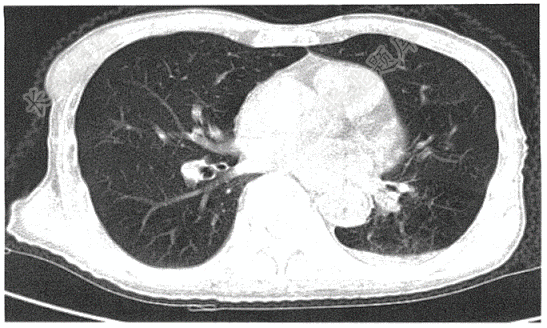

- 单项选择题请选出正确诊断( )

A、左下肺结节

B、左下肺结核

C、左下肺感染

D、左下肺感染伴胸腔积液

E、左下肺癌